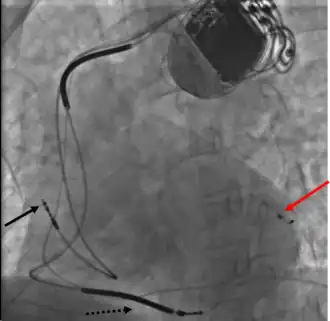

A terapia de ressincronização cardíaca (ing. Cardiac Resynchronization Therapy, CRT) - é um tratamento da , insuficiência cardíaca congestiva, que envolve o implante de eletrodos no coração para "cardioestimular" de forma sincrônica ambos ventrículos. Em alguns casos, também é possível estimular apenas o ventrículo esquerdo.

Na insuficiência cardíaca avançada, esse implante é utilizado para tratar um distúrbio da estimulação do ventrículo esquerdo (como dessincronia na contração). No eletrocardiograma, este fenômeno é acompanhado por ampliação do complexo QRS, sendo a origem de tal modificação, em muitos casos, o bloqueio do ramo esquerdo do feixe.

Outros nomes: estimulação de ressincronização, a estimulação de dupla câmara A assincronia sistólica entre os ventrículos esquerdo e o direito leva à contração antecipada do septo em relação à parede lateral do ventrículo esquerdo, o que dificulta o enchimento durante a diástole. Sendo assim, tal assincronia diminui o volume de ejeção sistólico.